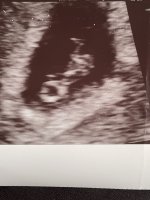

Wow! Gratulerer! To sett med tvillinger i gruppa så langtDa har jeg også vært på tul! Her var det to bankende hjerterVar egentlig litt forberedt da vi satte tilbake to blastoer (ivf) men allikevel et sjokk! Det nederste var litt mindre enn det andre 4 og 7 mm. Så litt usikkert hvordan det blir, ny ultralyd om en uke

målt til 5+5, satt en uke tilbake. Fikk se bankende hjerte